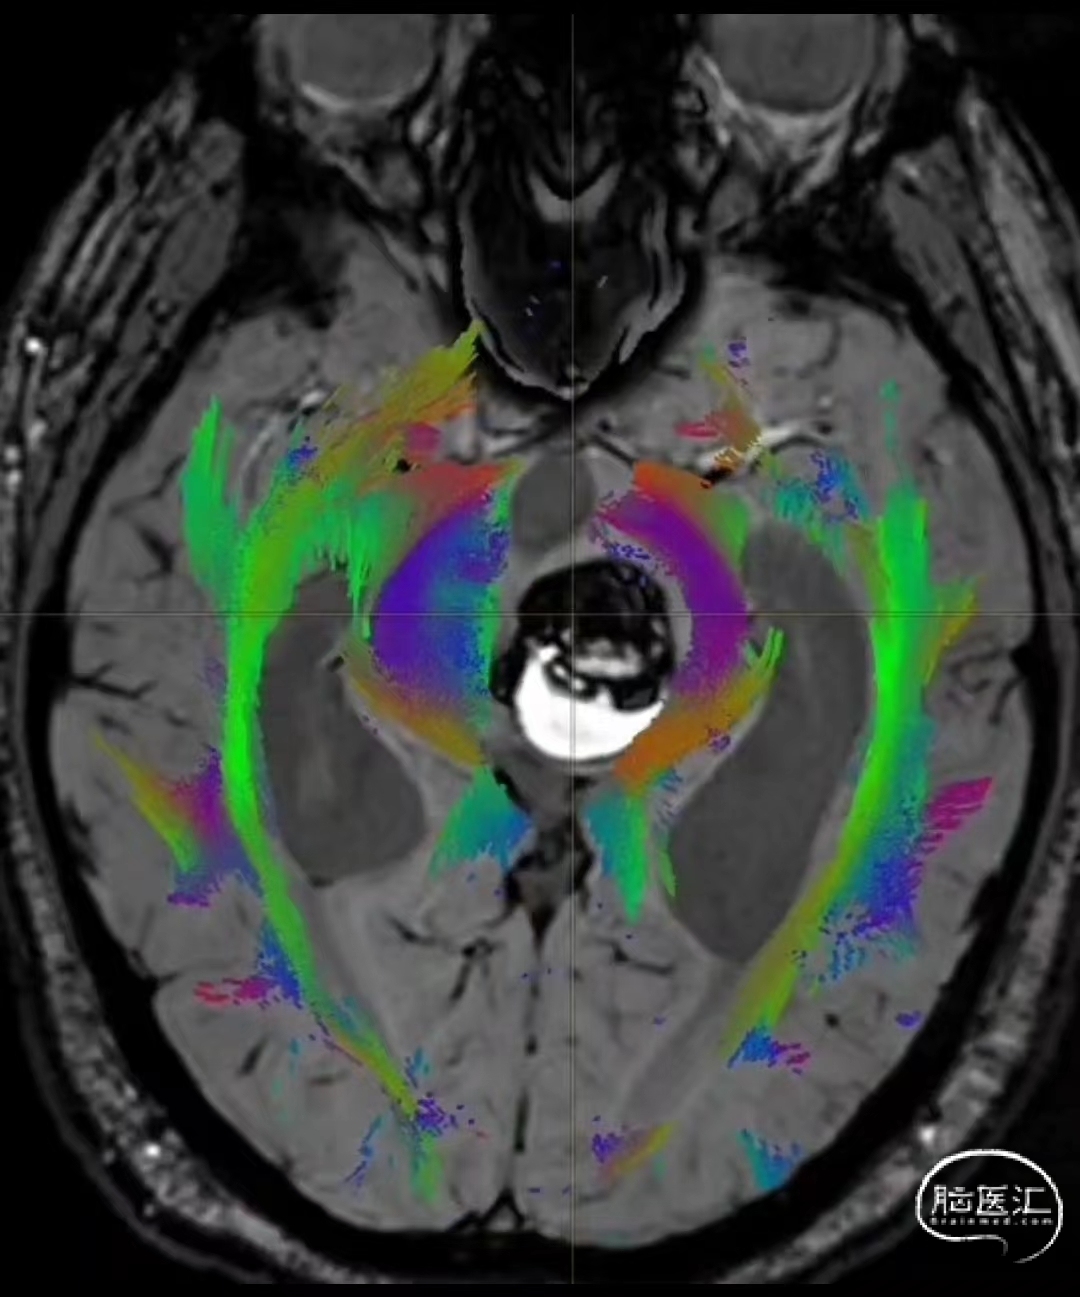

术前DTI检查

根据MRI及DTI显示,只有在丘脑与上丘之间的点(dot)进入病变才可能在切除病变时最大程度保护神经功能,由于上述原因,该“点”在术中显露极其困难,虽有导航指引,电生理监测的条件下,对术者的耐心、技术、经验及体能依然是极大的挑战;

术前详细的磁共振检查,包括平扫增强,SWI及DTI,可以规划出手术最适宜的路径及切入点;